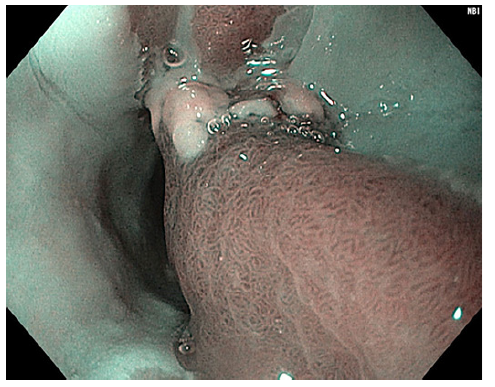

We repeated upper gastrointestinal endoscopy and observed two areas of pink mucosa oppositely positioned in the proximal esophagus (18 cm from the incisors), suggesting GH. One of these areas had a polypoid morphology with congestive, friable, and erosive mucosa measuring approximately 12 mm (Fig. 1). Narrow-band imaging evaluation showed a preserved glandular, vascular pattern (Fig. 2). Biopsies were taken from the lesion and anatomopathological assessment revealed fragments of gastric-type mucosa, consisting of occasional poorly oriented foveolar structures compatible with ulcerated GH. There was no metaplasia or dysplasia. No H. pylori-like microorganisms were observed in GH (Fig. 3). A multidisciplinary approach led us to decide on an expectant strategy due to its probable benign course. A follow-up endoscopy was performed, and the polypshowednosignificant changes from the prior examination.

Fig. 1 Congestive and friable polyp arising from esophageal inlet patch in the proximal esophagus, in contralateral position to another inlet patch.